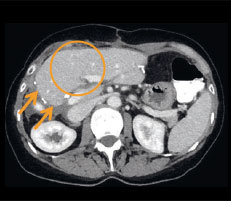

Abb. 1b

Ergebnis nach IRE: In der Mitte zeigt sich die vollständig abgetötete Metastase nach der Ablation als dunkle Zone innerhalb des hellen, gut durchbluteten Lebergewebes (siehe Kreis).

Je nach Behandlungsfeldgrösse und Sondenanzahl dauert die Ablation zwischen einer und zehn Minuten. Die ­exakte Platzierung der Sonden ist jedoch der wichtigste Schritt und nimmt ein Vielfaches dieser Zeit in Anspruch. Mittels dreidimensionaler computer- oder magnetresonanztomographischer Kontrolle wird direkt im Anschluss an die Ablation überprüft, ob das Tumorgewebe ausreichend abgetötet wurde. Im Fall von Frau O. wurde das Gewebe vollständig erfasst: Sichtbar ist eine dunkle Zone innerhalb des ansonsten hellen, gut durchbluteten Lebergewebes (Abb. 1b). Die IRE-Behandlung wird in Vollnarkose durchgeführt. Ein Krankenhausaufenthalt ist bei ­einer nicht operativen Anwendung nicht zwingend notwendig, wird jedoch zur Sicherheit des Patienten empfohlen.